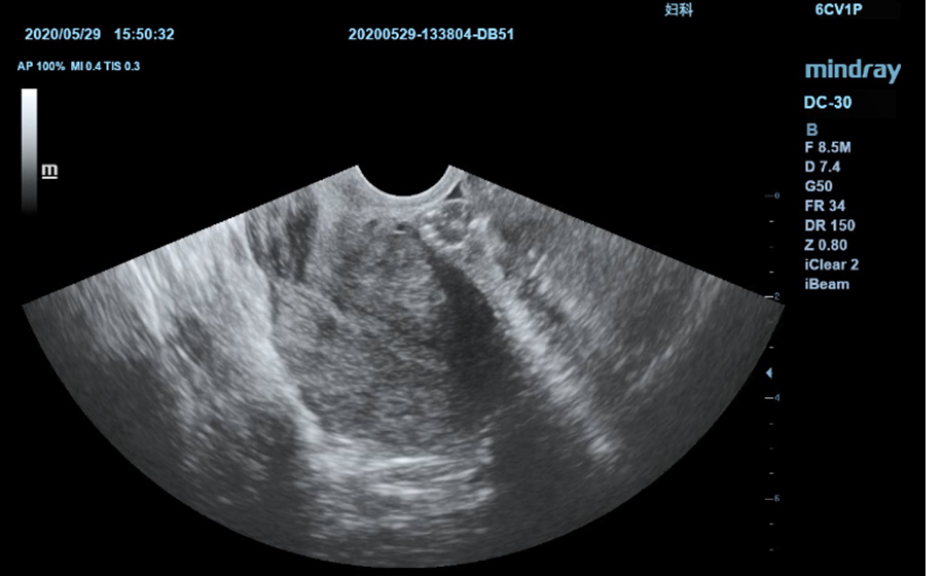

Ilustraciones anatĂłmicas normales que incluyen imĂĄgenes esquemĂĄticas y ecogrĂĄficas.

VisualizaciĂłn lateral de ultrasonografĂas estĂĄndares que proporciona orientaciĂłn visual sobre la regiĂłn de interĂ©s.

ImĂĄgenes de ecografĂas estĂĄndares

3

ComparaciĂłn de ecografĂas en tiempo real para su referencia.

ImĂĄgenes de ecografĂas de referencia

ImĂĄgenes clĂnicas